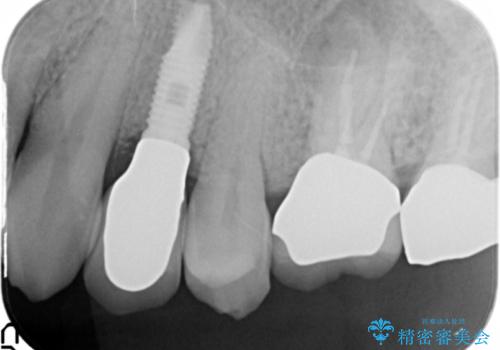

歯科治療や外科手術が苦手な患者様で、治療前はとても怖がっていましたが、インプラント手術後には「思ったよりも大変ではなかった」とおっしゃって下さいました。

元の歯のように咬むことができ、見た目も自然だと喜んで頂けました。

インプラントの種類:スプライン ツイスト

被せ物の種類:メタルボンドクラウン

固定様式:スクリュー固定